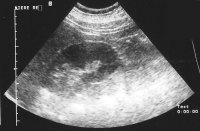

In der Sonographie fand sich eine kleine Niere links bei unauffälliger rechter Niere (Abbildung 18b).